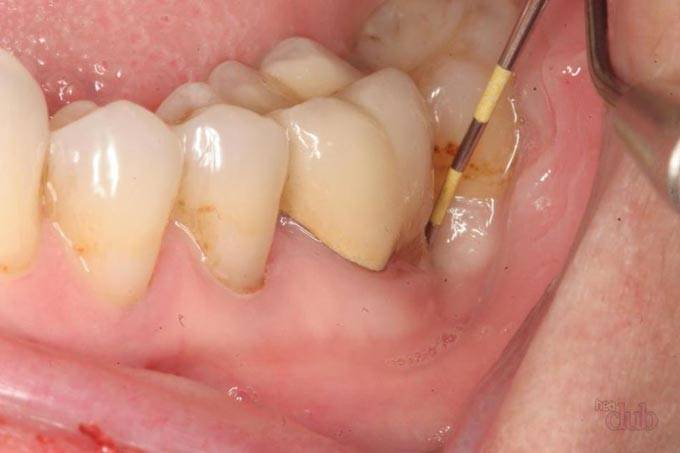

При пародонтите вдоль поверхности корней зубов формируются пародонтальные карманы, из которых в периоды обострения отходит гнойное отделяемое. Если пародонтальный карман очень глубокий, то отток гноя из него может нарушаться. В этом случае в проекции пародонтального кармана между десной и корнем зуба формируется гнойник, который стоматологи называют термином «пародонтальный абсцесс». Одним из исходов пародонтального абсцесса может стать и формирование свища, через который гной будет выходить в полость рта.

Такая ситуация характерна для пациентов с хроническим воспалением десен – пародонтитом. При этом заболевании образуются глубокие десневые карманы, в которых скапливается налет и зубной камень вкупе с бактериями и микробами. По мере увеличения патогенные образования разрушают зубо-десневые связки, а отток гноя из них затрудняется. Это приводит к образованию пародонтального абсцесса. Впоследствии в его проекции появляется свищевой ход.

Заподозрить, что фистула сформировалась из-за пародонтита можно по глубоким десневым карманам и здоровому, ранее не леченному зубу в проекции свища.